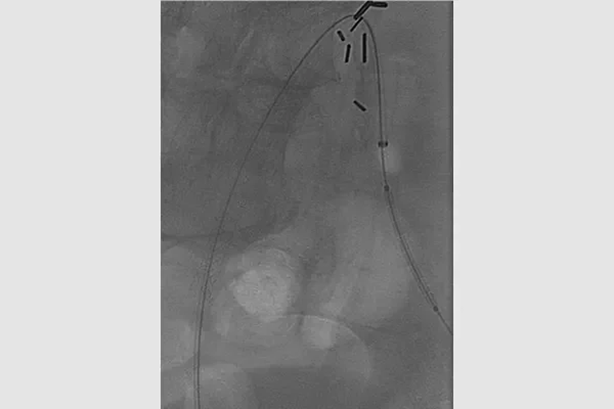

对侧入路

gore医疗怎么样首批患者已入组GORE VBX FORWARD临床研究——VBX支架与裸金属支架在治疗髂动脉闭塞性疾病中的比较_https://www.jmylbn.com_新闻资讯_第6张